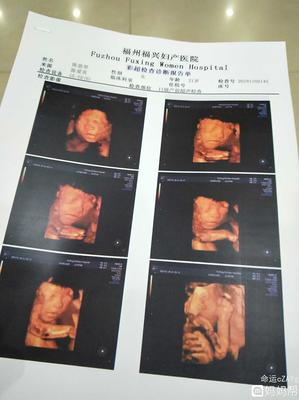

这份沉甸甸的希望,最终落在了福州福兴妇产医院的土地上。这里,不再仅仅是一个医疗机构的名字,它成为了一个承诺的承接者,一个新生故事的起点。当母亲带着孤注一掷的决心踏入这里,医院的白墙与灯光,便成了守护这份希望的第一道屏障。专业的医护团队,用他们的知识与经验,将那句“希望你能好好的”朴素愿望,转化为了严谨的产前检查、周密的健康评估和全天候的悉心监护。他们明白,他们守护的不仅是一个婴儿的平安降生,更是一个家庭用巨大勇气换来的珍贵未来。

产房里,每一次胎心的跳动,都像是在回应那份执着的坚持;每一次顺利的检查结果,都是对“留下”这个决定的一次温柔肯定。福州福兴妇产医院提供的,从先进的医疗技术到人性化的关怀服务,共同编织成一张安全网,托住了这个被深切期盼的小生命。母亲曾经的“拼命”,在这里化为了科学的护航与温暖的陪伴。